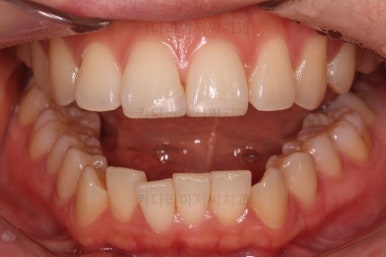

마찬가지로 부산연산동교정치과 초진 시 입안의 모습입니다.

눈에 띄는 것은 윗니 안쪽 치아 하나가 아예 입천장쪽으로 나서 매우 삐뚤어요.

저렇게 삼각혁으로 배치되어 있는 치아는 셋 중 하나는 꼭 썩어요.

셋 사이에 음식물이 잘 끼고 양치가 힘들기 때문이죠.

아래 앞니도 삐뚤한 편이었고 아래 앞니가 불쑥 위로 올라와 있어서 이를 악 다물면 위아래 앞니가 많이 겹치는 "과개교합" 패턴이 나타나요.

윗니가 전반적으로 아랫니보다 앞에 나와 있어서 2급 부정교합에 윗니만 튀어나온 양상이고 이 때문에 윗니 앞니가 다치고 부러졌따가 떼운 흔적이 보이네요.